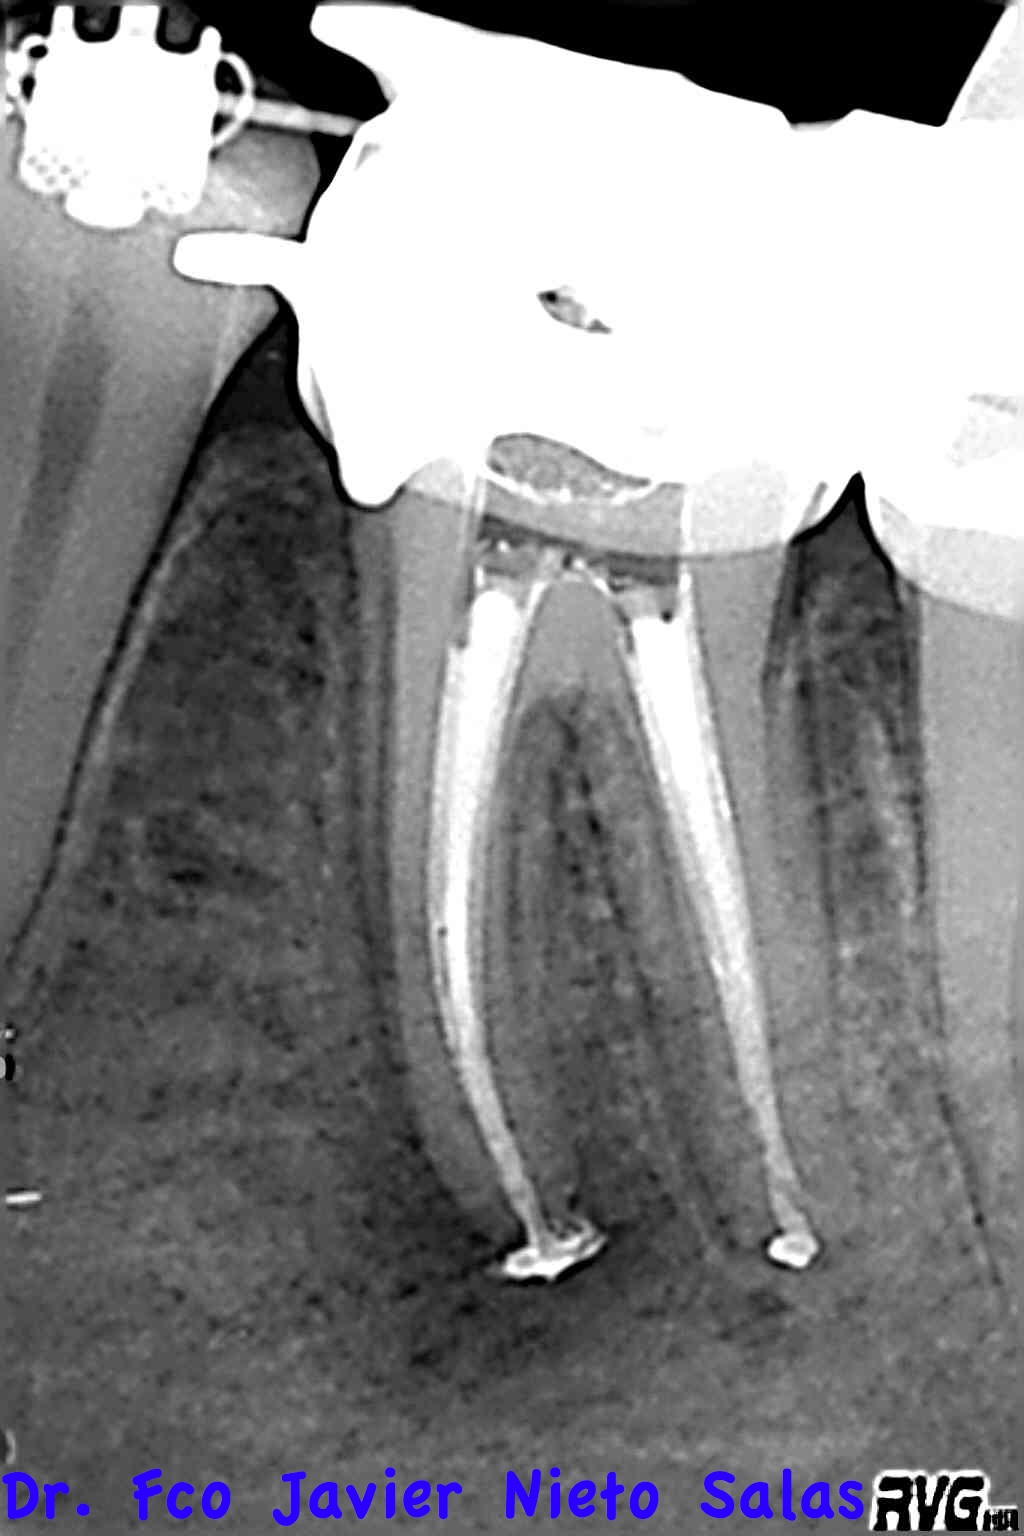

Usamos la técnica de ola continua de calor descrita por Buchanan y el backfilling se hizo con gutapercha inyectada.

Se citó a revisión a los nueve meses, no presentaba sintomatología y los signos claros de evolución positiva.